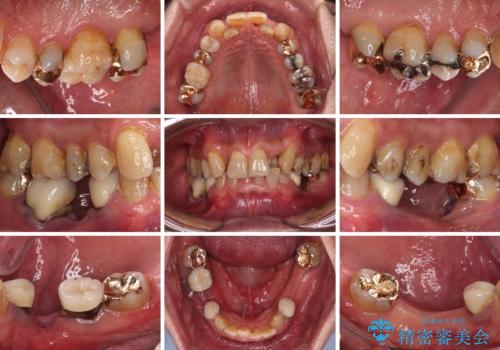

- 下顎両側の欠損と上顎前歯のデコボコを気にして来院された患者様です。

デコボコは今まで気にせずにいたそうですが、奥歯の欠損改善を機に、矯正治療に興味があるので、相談したいとのことでした。

奥歯に欠損が多く、矯正治療はやや難航することが予想されますが、患者様の希望もあり、上顎左右小臼歯を1本ずつ抜歯し、ワイヤー装置にて矯正治療を行うこととしました。

矯正歯科治療を行うに当たり、痛みや違和感を感じている歯の根管治療を行い、矯正治療中にインプラント埋入し、補綴治療と矯正治療を同時に終了できるように進めて行くこととしました。

銀歯やむし歯治療されている歯を抜歯する治療計画としたため、やや時間はかかりましたが、治療後の仕上がりには大変満足していただけました。